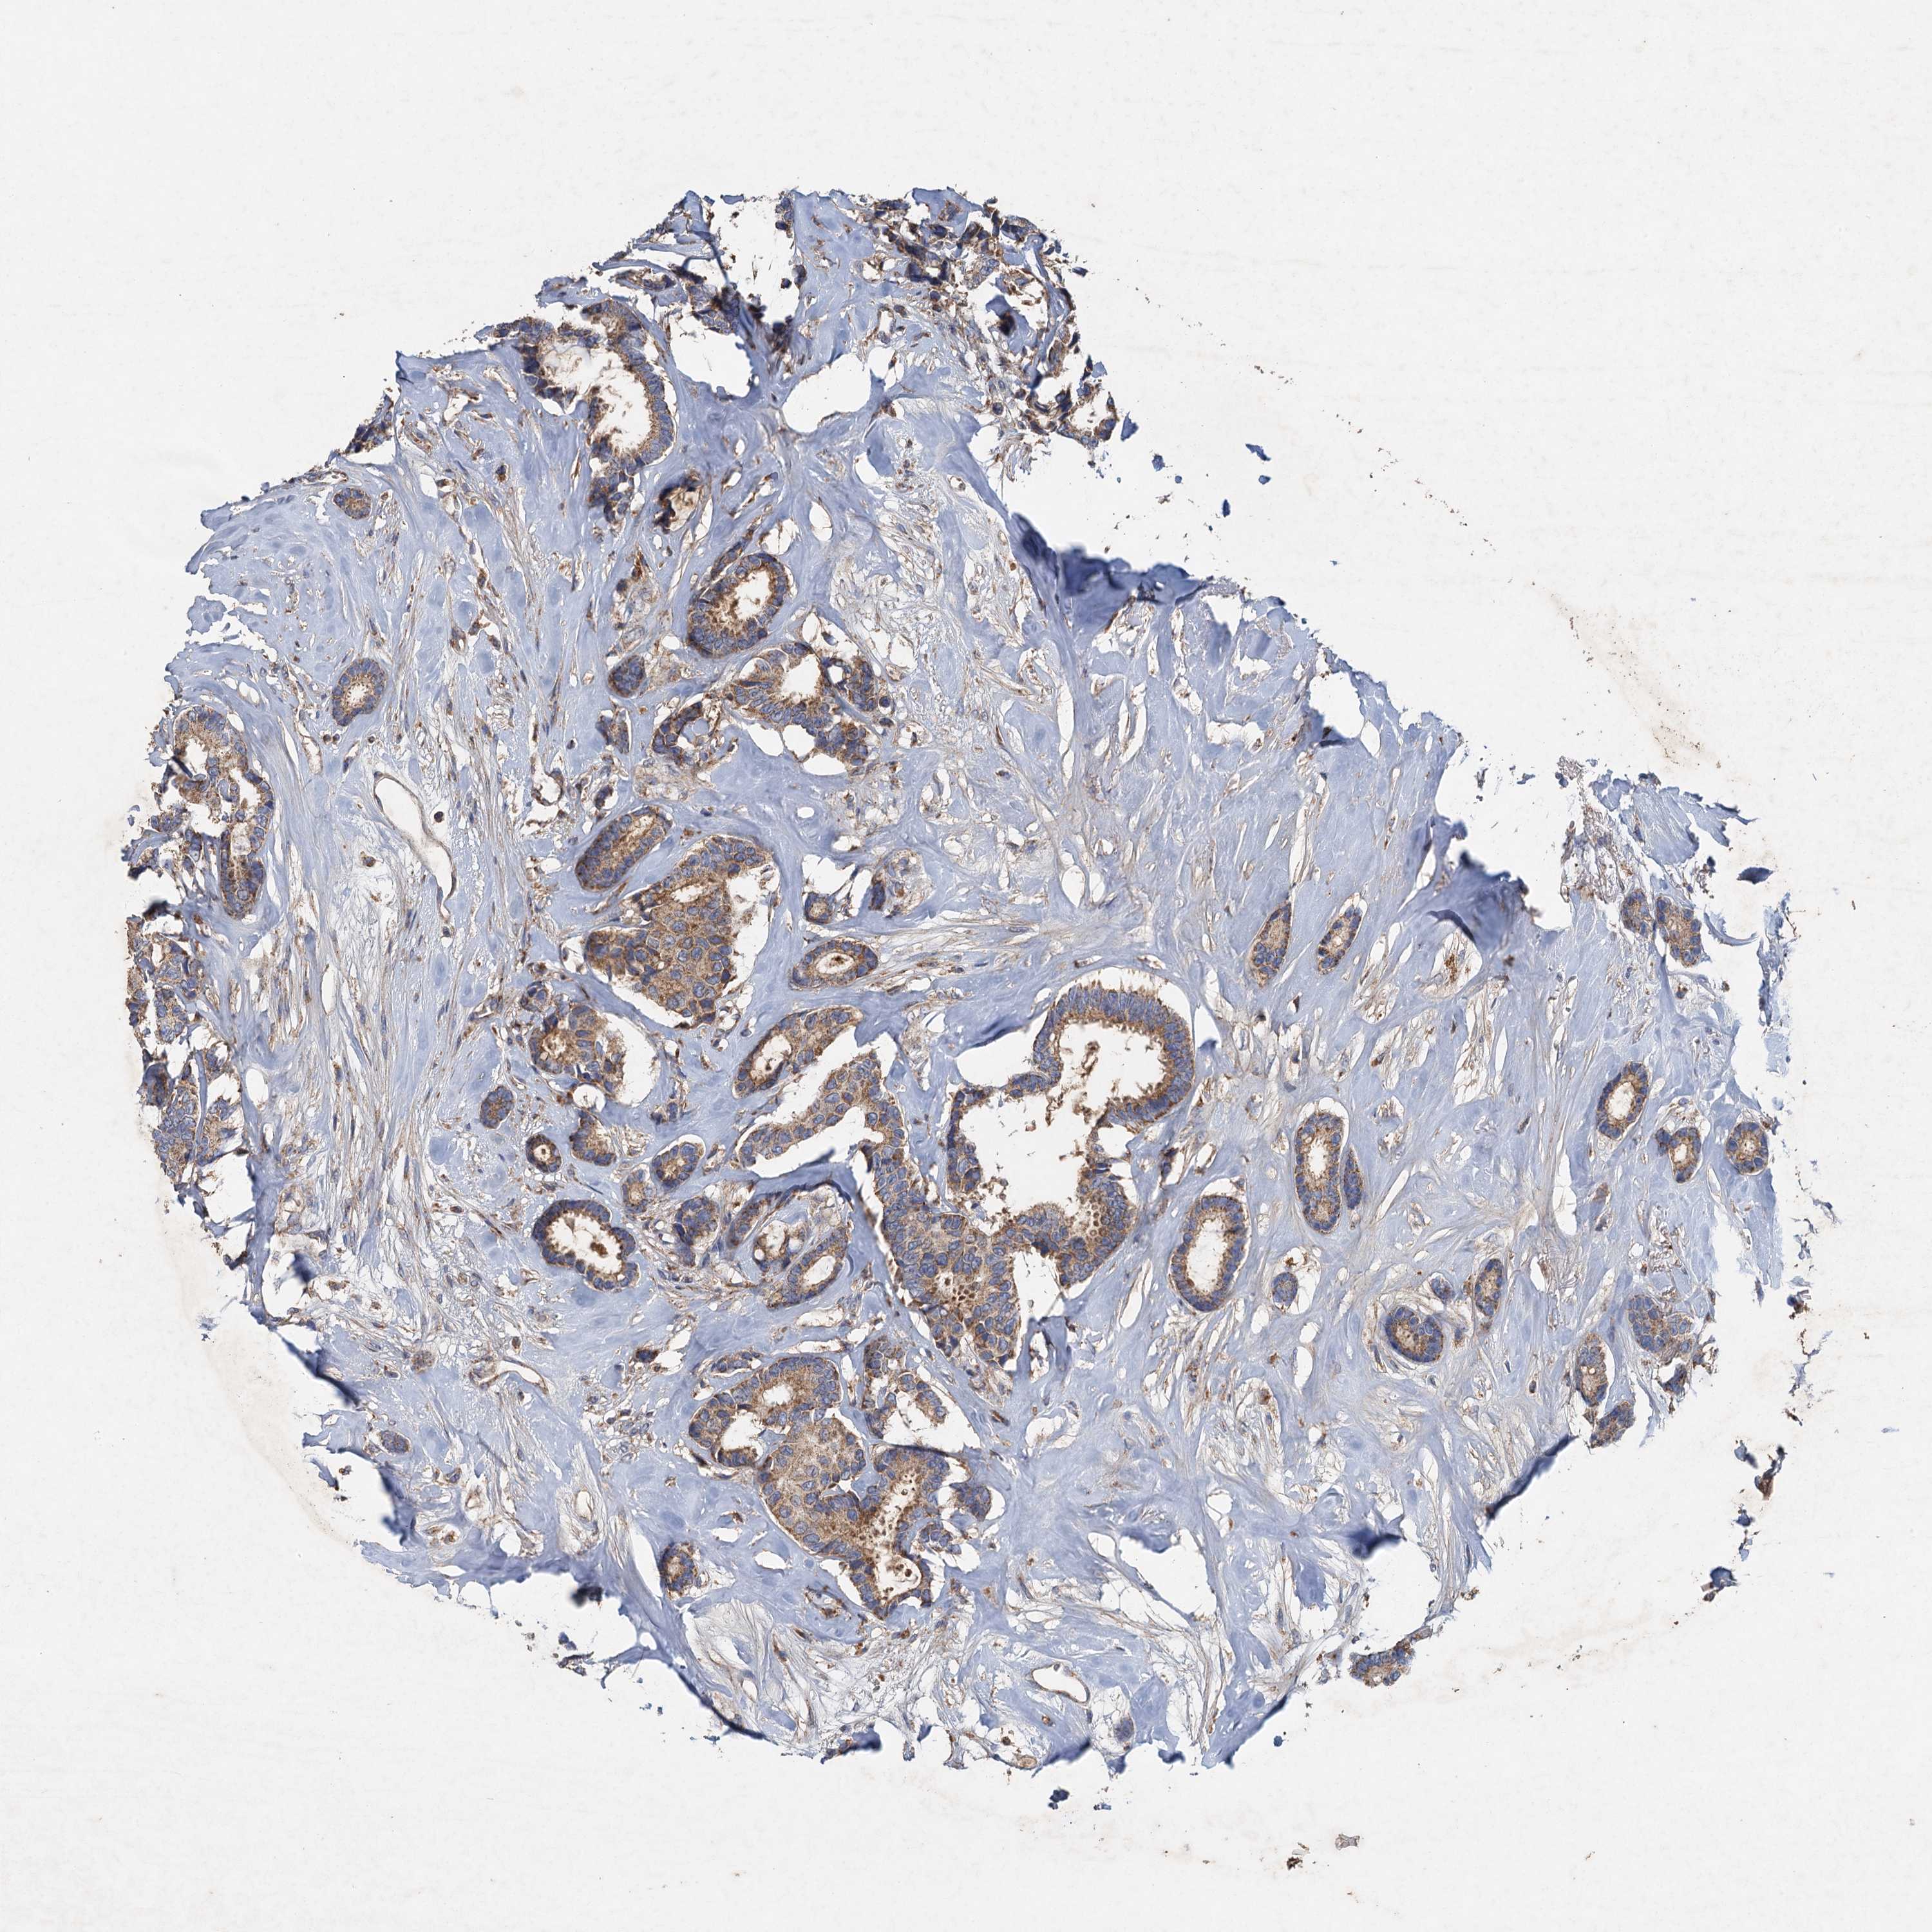

BRCA TCGA BRCA VALIDATION PROTEIN EXPRESSION